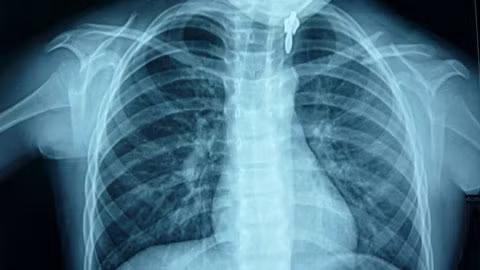

| Kết quả chụp phim sáng ngày 28/9 của bé Anh - Ảnh: Vietnamnet.vn. |

Trao đổi với chúng tôi, bác sĩ Huỳnh Bá Lĩnh, người trực tiếp điều trị cho bé Anh cho biết ngay từ hôm 24/9, khám cho bé, sau khi loại trừ hết các khả năng gây chấn thương như bị đánh, bị té ngã thì nguyên nhân kết luận gây gãy xương đòn chính là do đeo cặp sách quá nặng. Ngoài ra, bệnh nhi còn bị gù và vẹo cột sống.

Do bé còn nhỏ, các bác sĩ tránh phẫu thuật, cố gắng nẹp để ép phần xương nhô lên xẹp xuống trở lại. Đối với người lớn, gãy xương đòn có thể để lại di chứng làm cho vai ngắn lại, bị lệch.